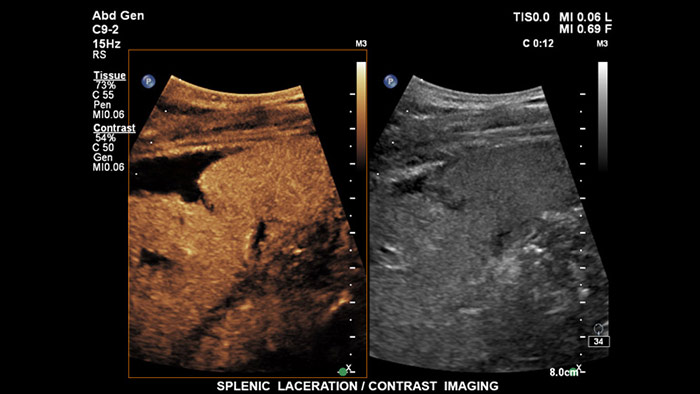

La tecnología PureWave Crystal supone el mayor avance en material de transductores piezoeléctricos en 40 años. Los cristales de PureWave son puros y uniformes, un 85 % más eficientes que el material piezoeléctrico convencional, con lo que se obtiene un rendimiento excepcional. Esta tecnología está integrada en nuestros transductores C5-1, C9-2 y X6-1 y permite una mejor penetración en pacientes con dificultades técnicas, al tiempo que mantiene excelentes resultados en cuanto a resolución de detalles, sensibilidad Doppler y rendimiento de CEUS.

Los agentes de contraste para ultrasonidos pueden transformar el papel que desempeñan los ultrasonidos hepáticos, pues permiten que el usuario estudie los patrones de mejora de las lesiones hepáticas sospechosas en tiempo real, lo que ofrece la posibilidad de realizar diagnósticos más fiables y rápidos. Con EPIQ de Philips, los CEUS se integran a la perfección en el flujo de trabajo normal y proporcionan un nivel de detalle excepcional en exploraciones de la fase arterial, portal y tardía. Además, EPIQ ofrece el mayor nivel de fiabilidad posible para la detección y caracterización de lesiones, incluso en las exploraciones más difíciles; esto es posible gracias a tecnologías avanzadas al alcance de su mano, entre las que cabe mencionar las siguientes: pantalla MaxVue FHD, transductor PureWave C9-2, imágenes de fusión y cuantificación Q-App.

Los agentes de contraste para ultrasonidos pueden transformar el papel que desempeñan los ultrasonidos, pues permiten que los profesionales sanitarios estudien los patrones de mejora de las lesiones hepáticas en tiempo real, lo que ofrece la posibilidad de realizar diagnósticos más definitivos y rápidos. Con los ultrasonidos de Philips, los ultrasonidos con contraste se integran a la perfección en el flujo de trabajo normal y ofrecen un nivel de detalle excepcional.